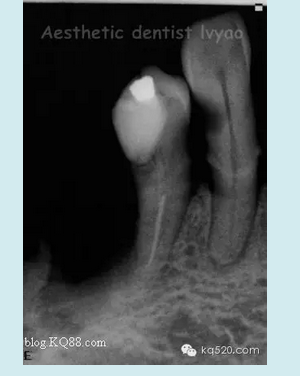

右下34修復(fù)前X片(牙槽骨吸收,基牙達(dá)到2度松動(dòng))